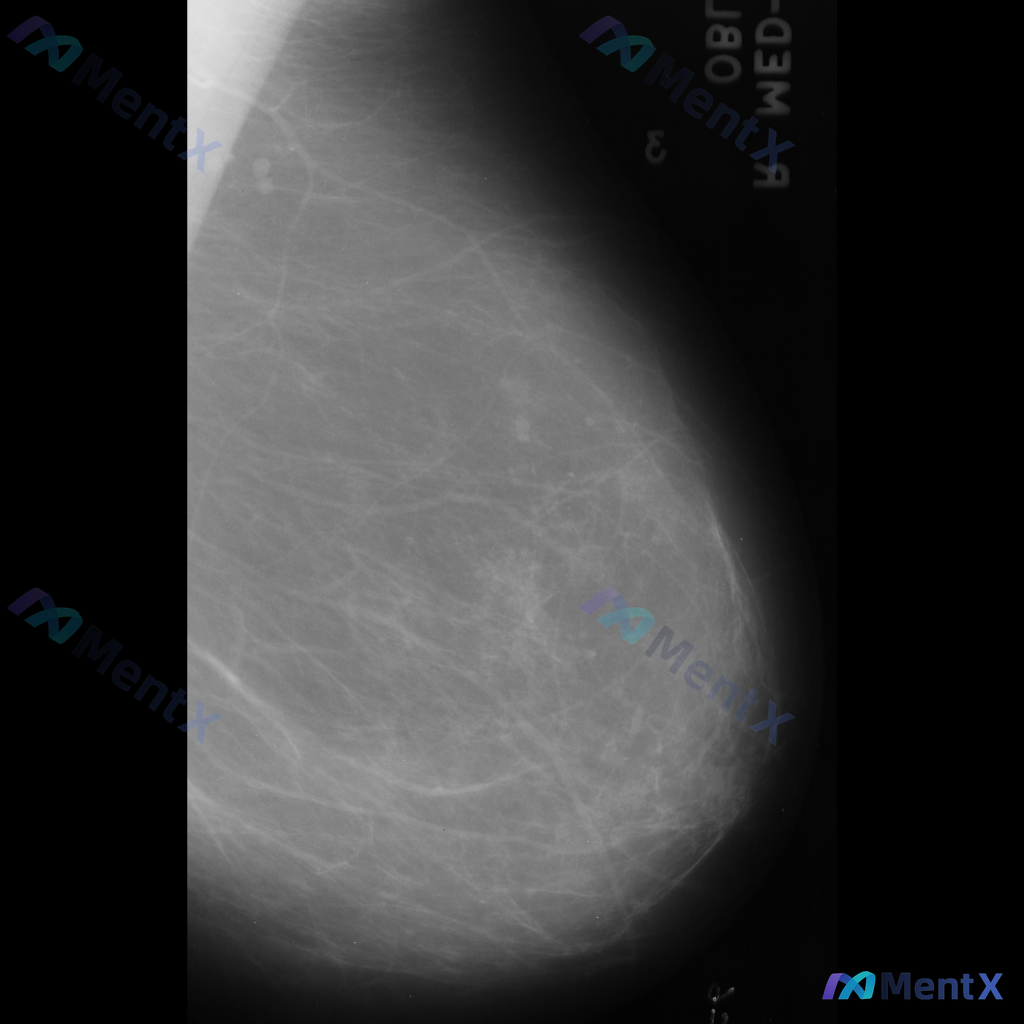

整理到一份右侧乳腺钼靶的影像资料,先和大家说一下表现: - 背景为不均匀致密型乳腺 - 右侧乳腺中部偏上区域可见局限性、成簇的细小多形性钙化 - 钙化区域周围可见局部密度略增高/结构异常的表现 目前还没有进一步的检查结果,单看这组影像表现,大家会优先往哪个方向考虑?后续评估思路是什么?